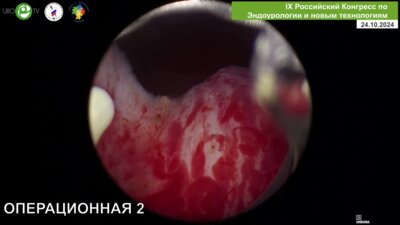

Uro.TV

Сорокин Николай Иванович

д.м.н., профессор, руководитель урологической службы МНОЦ МГУ, ведущий научный сотрудник ФФМ МГУ им М.В. Ломоносова